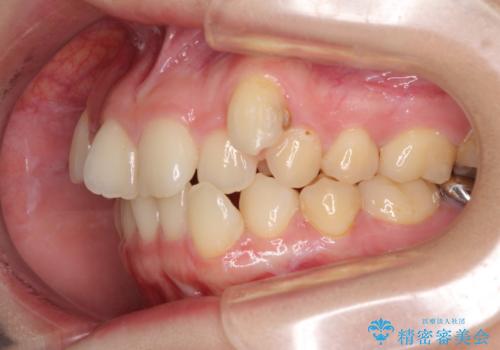

上顎の八重歯と下顎前歯の欠損 ワイヤー装置による抜歯矯正

- 上顎の八重歯を気にして来院された患者様です。

診察したところ、下顎前歯が2本欠損していたため、上下のバランスを取りながら八重歯を改善するため、上顎左右第一小臼歯2本を抜歯することとしました。

下顎左右大臼歯の歯根部に病変があったため、矯正治療前に根管治療を行い、矯正治療後にセラミッククラウンによる補綴治療を行うこととしました。

下顎前歯と本来抜歯矯正で抜歯する歯とは大きさが異なるため、仕上がりの咬み合わせは理想的なものとはなりませんでしたが、気になっていた八重歯はきれいに改善することができました。